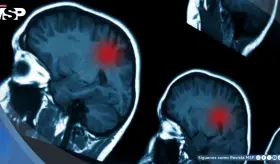

Su diagnóstico comienza de manera incidental, cuando se realiza una resonancia magnética cerebral por otros motivos médicos y se identifica la presencia de la lesión.

La experta diferencia entre fatiga y deterioro cognitivo, señalando que los signos preocupantes serían otros, y que las imágenes observadas no permiten concluir nada por sí solas.